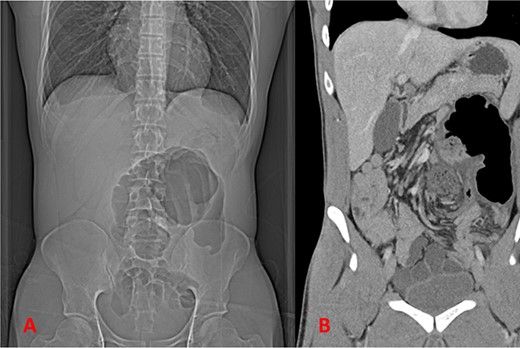

A healthy patient in his 20s, with no previous abdominal surgical history, presented to the emergency department with a 1 day history of acute onset abdominal pain. The patient presented with normal vital signs and normal labs. His physical exam was notable abdominal distention as well as significant lower abdominal tenderness and rebound, consistent with focal peritonitis. Computed tomography (CT) scan of the abdomen and pelvis was obtained which revealed volvulus of a segment of large intestine with radiographic findings concerning for ischemic changes (Fig. 1A and B). Imaging was concerning for a large bowel volvulus. As a result, it was recommended to proceed to the operating room for exploration given concern for ischemia.

Imaging showing findings concerning for volvulus of the large intestine; (A) plain film of abdomen; (B) coronal CT imaging.